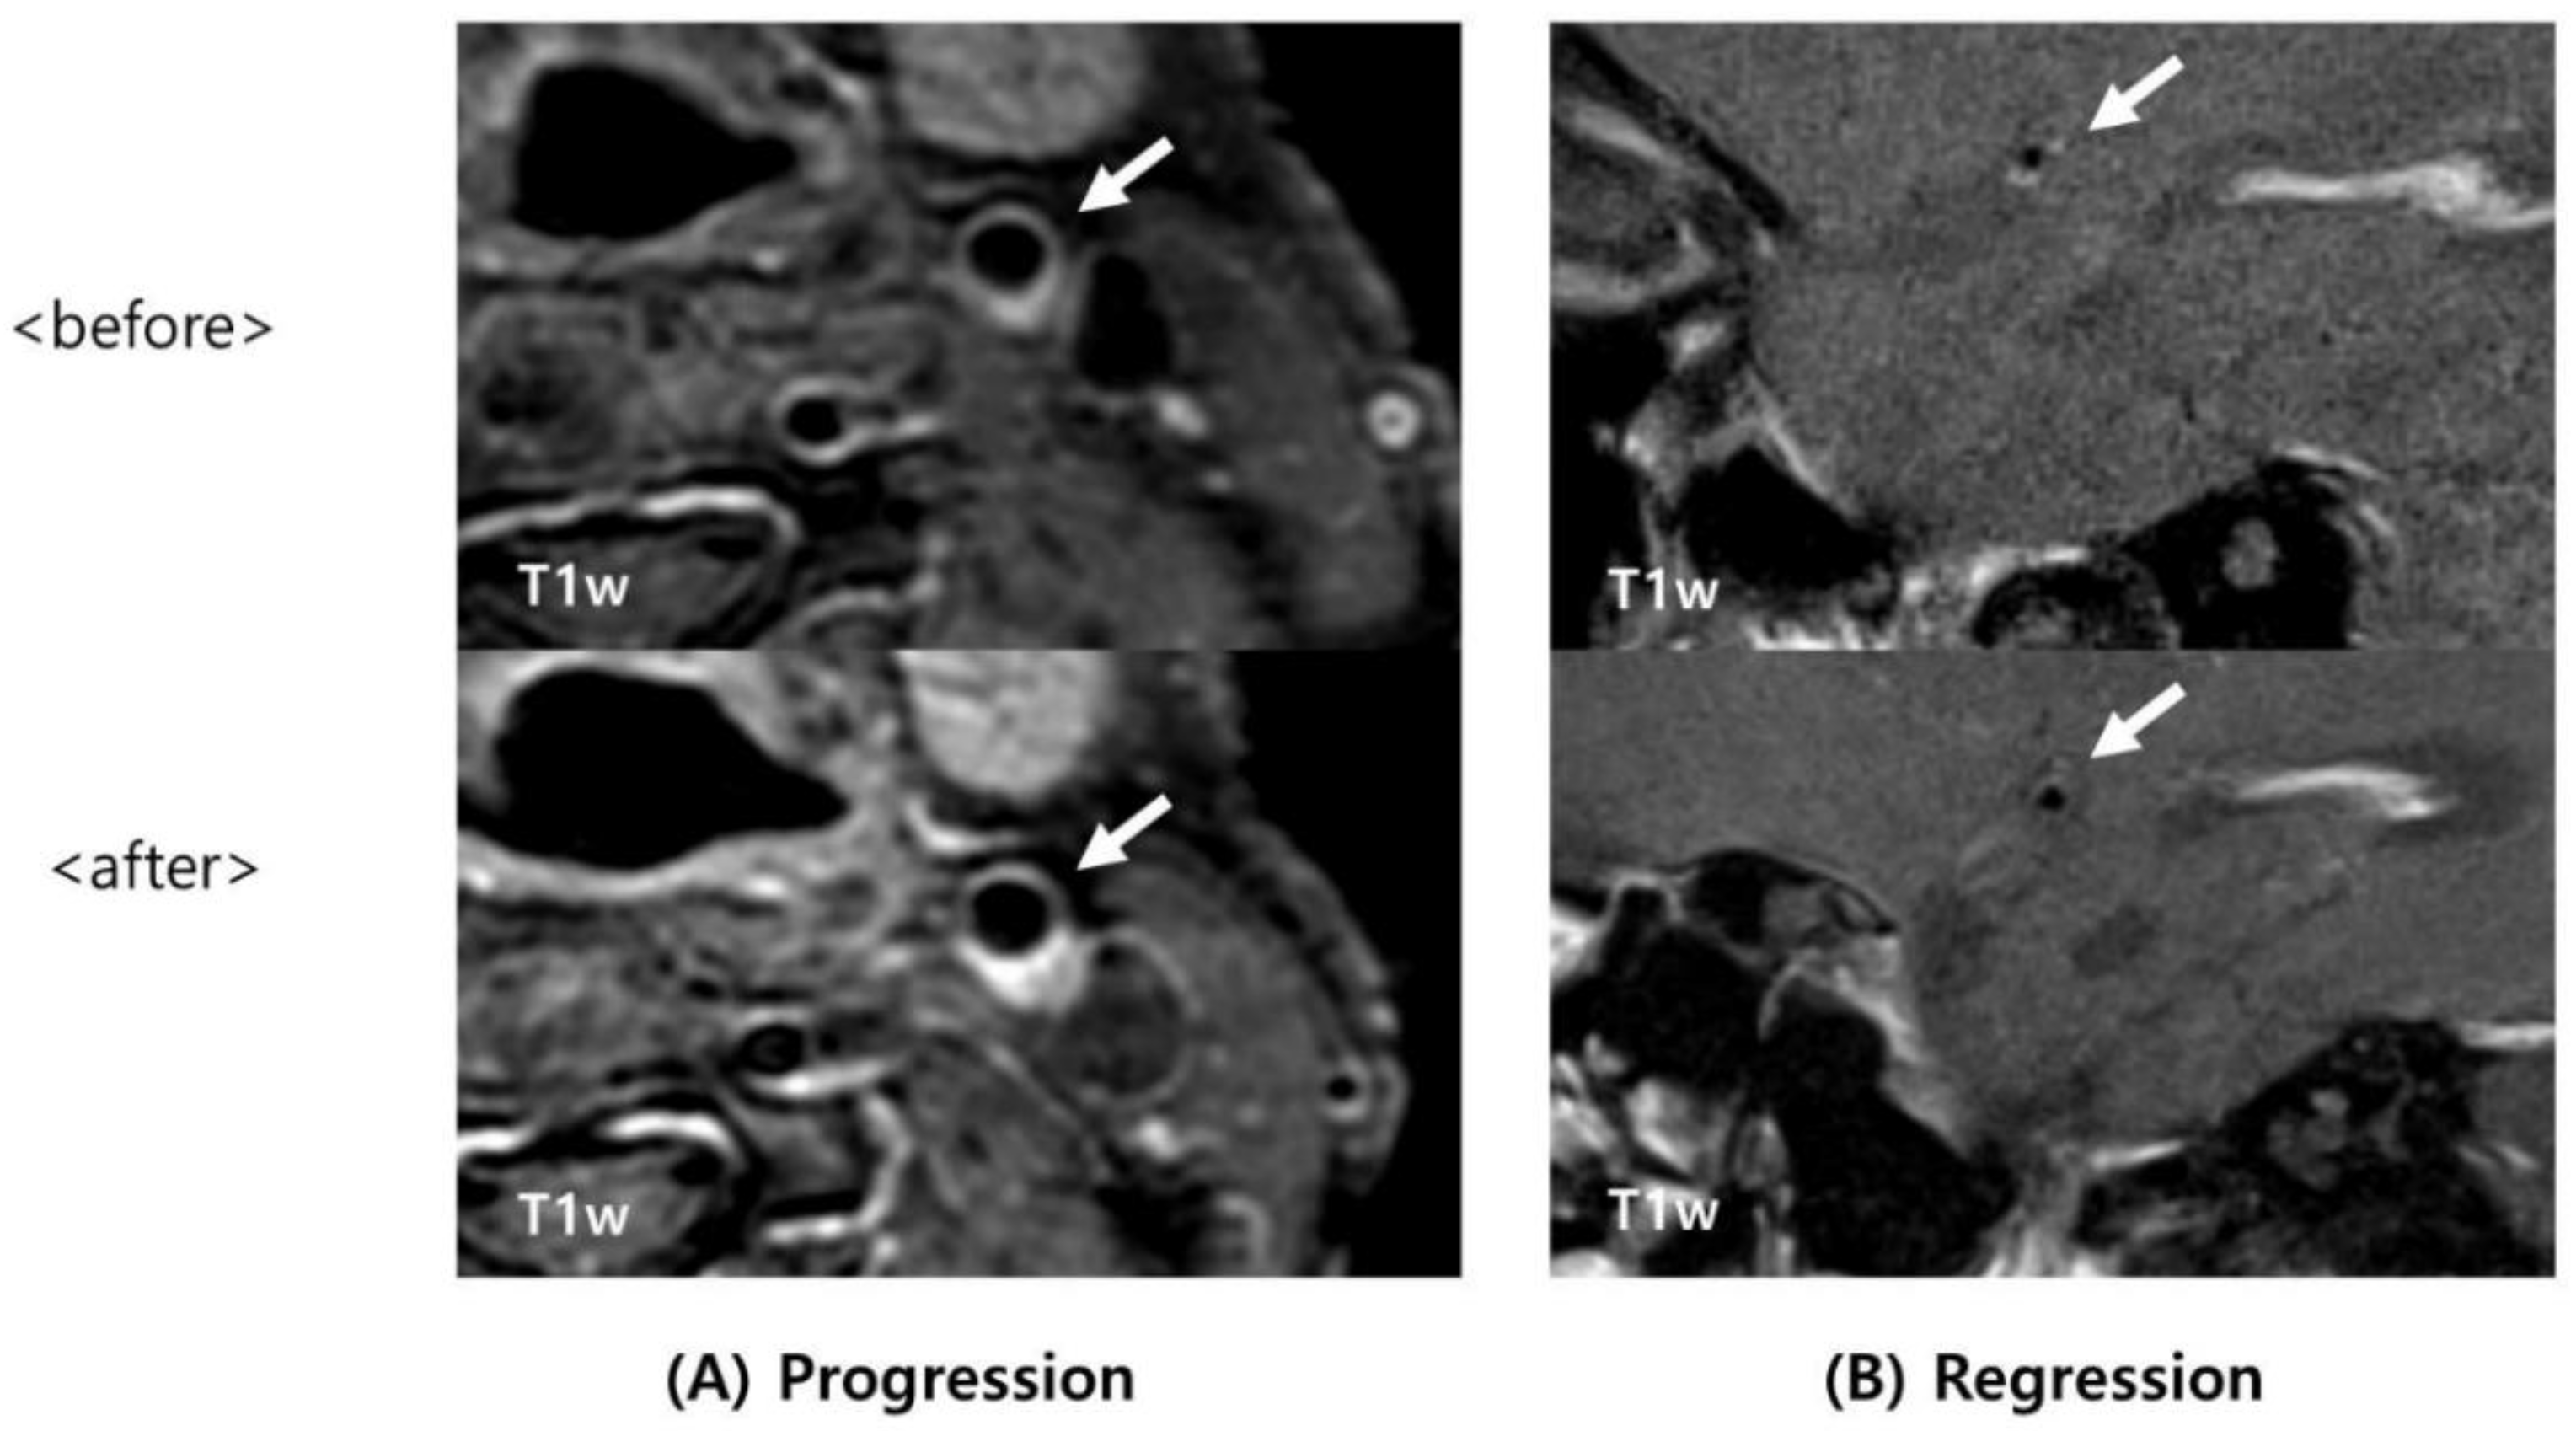

2.4. Image Analysis